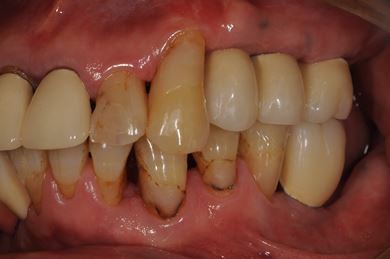

骨再生スピードインプラント治療+遊離歯肉移植

| 性別/年齢 | 男性 / 66歳 | ||||||||||||||||||||||||||||||||

| 主訴 | 入れ歯の部分をインプラントにしたい。 | ||||||||||||||||||||||||||||||||

| 治療内容 | インプラント8本(サイナスリフト、抜歯即日スピードインプラント)、ハイブリッドセラミッククラウン9本、遊離歯肉移植 | ||||||||||||||||||||||||||||||||